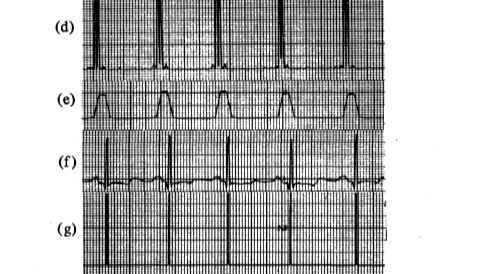

实时检测QRS波

Pan-Tompkins心电QRS检测算法